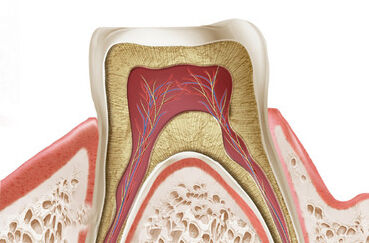

Molares Decíduos Anquilosados Nesta curso online vamos conversar sobre a Anquilose de Molares Decíduos. Qual a implicação clínica da anquilose? Qual a conduta diante da